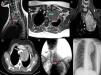

En la TAC se describe una masa de 6×7×11cm desde región tiroidea izquierda hasta hilio pulmonar, desplazando medialmente la arteria carótida interna y posteriormente la arteria subclavia, en contacto con el cayado aórtico y la arteria pulmonar (fig. 1D). En la RMN muestra realce con gadolinio (fig. 1A-C). En la angiografía de troncos supraaórticos existe un stop a nivel de vasos subclavios (fig. 1E).

A y B) Desplazamiento medial y anteroposterior de la arteria carótida y de la arteria subclavia, respectivamente. C y F) Extensión cérvico-mediastínica tumoral (Ao: arco aórtico). D) Relación del tumor con el tronco arterial braquiocefálico derecho. E) Gradiente de bajo flujo en vasos subclavios.